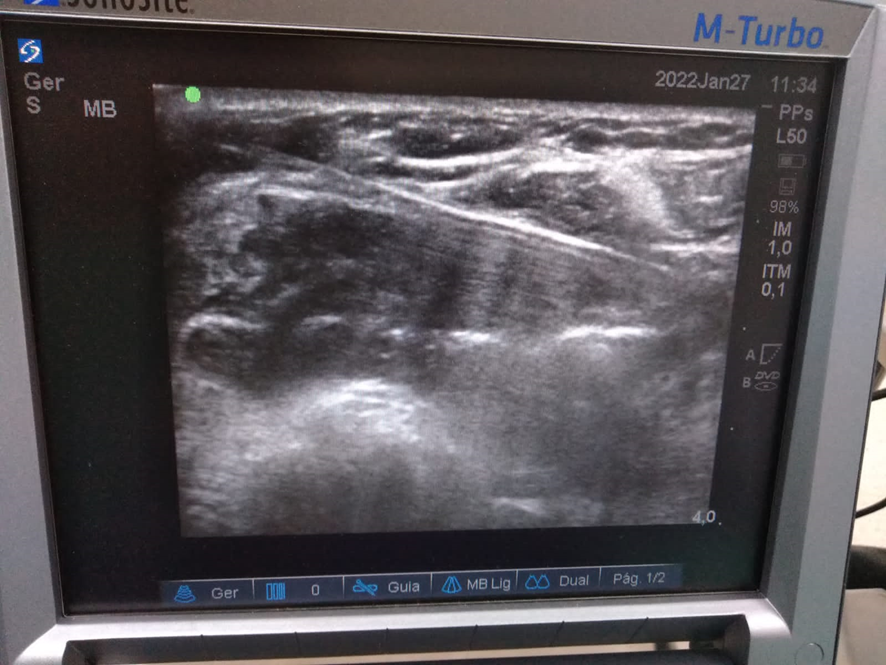

A radioablação é uma técnica em que é feita a ablação do nódulo da tireoide por radiofrequência, com uma agulha que aquece e destrói o nódulo gradativamente.

Neste método, o nódulo é “exterminado” garantindo total funcionalidade da glândula. Esse é um dos grandes benefícios desta técnica em relação à cirurgia de remoção da tireoide, em que o paciente precisa repor o hormônio produzido por meio de medicamentos.

Na tireoide, o maior benefício é remover o nódulo pelas ondas de radiofrequência sem remover a glândula da tireoide. E para o paciente, os benefícios são imensos já que não existe corte nem cicatriz e que as funções hormonais são preservadas, a anestesia é local, o Paciente fica cerca de três a quatro horas internado, não é entubado. Dentre as principais vantagens, temos a que o Paciente, mesmo sendo câncer, não precisa tomar o hormônio da tireoide, evitando a reposição sintética. Portanto uma vantagem é que na ablação os pacientes não precisam tomar hormônios após o tratamento! É preciso entender o critério de cada caso para saber se a radioblação é indicada ou não.